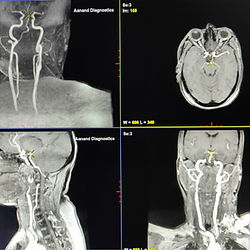

Digital MRI (AIR Recon DL)

Experience the "Fast" MRI Difference : We are proud to offer Kota’s advanced and only Digital MRI with AIR Recon DL technology. Unlike traditional MRI machines that are loud and slow, our system is designed for patient comfort while delivering 3T-quality equivalent images for superior diagnostic accuracy. We provide all advanced Digital MRI services powered by AIR Recon DL technology, delivering up to 50% sharper images while significantly reducing scan time. To ensure a comfortable experience, we also offer MRI‑compatible music headphones that help patients feel relaxed throughout the procedure. All kind of MRI scans are available like : MRI Breast (3D Dynamic Study) MRI Spectroscopy MRI Brain Angiography MRI Brain Venogram MRI Brain Epilepsy Protocol MRI Spine MRCP MRI Abdomen Contrast MRI MRI Knee MRI Shoulder MRI Pelvis MRI Prostate with PIRAD Score Why Aanand Diagnostics is Best for MRI Test in Kota : *AIR Recon DL Software *Less Scan Time *Increased Image Quality *Reduced Noise and Ringing *Better Patient Experience *Available Compatible Music Headphones *Available MRI facility in case of Metal Implants Safety Note: Patients with pacemakers or metallic implants must inform the staff before entering the MRI room. Scan Timings : Mon - Sat : 9AM to 8PM Sun : Emergency Only Timings may vary